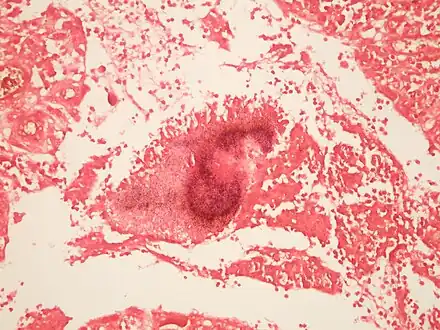

Micrograph of actinomycosis, GMS stain Micrograph of actinomycosis, Gram stain

Micrograph of actinomycosis, Gram stain